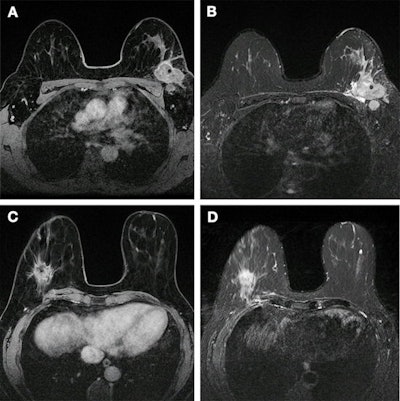

Ramtohul and co-authors wanted to find out whether multiparametric MRI-based radiomic features could help differentiate HER2-zero, HER2-low, and HER2-positive tumors. They tested their method on women with breast cancer who underwent MRI at two different centers between 2020 and 2022. The team also performed tumor segmentation and radiomic feature extraction on T2-weighted and dynamic contrast-enhanced T1-weighted images.

The team extracted a total of 101 features from 2D T2-weighted images and 107 features from 3D T1-weighted images. After unsupervised correlation analysis, 31 features were entered into the feature selection model. This included 14 T2-weighted and 17 dynamic contrast-enhanced T1-weighted images. The team obtained a radiomic signature using logistic regression of the top seven least absolute shrinkage and selection operator (LASSO)-selected features. This separated HER2-low and HER2-positive cancers from HER2-zero cancers.